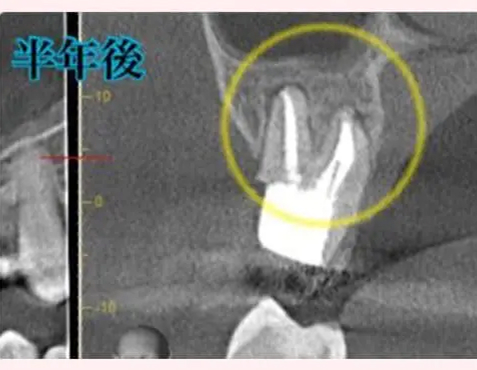

根尖病変によりCT上で黒く写っていた部分が白っぽくなっているのがわかりますか?

溶けていた部分の歯槽骨が回復しているということです!

また、上顎洞の肥厚は収まり、頬側の歯槽骨もくっきり映っています。予想以上に歯槽骨が回復しているので、今後外科的処置をしなくても良いのではないかと判断しました。大きなダメージがあった歯なので補綴物を入れた後も欠かさずに経過観察を行い、少しでも長くご自身の歯で生活して頂きたいと思います。